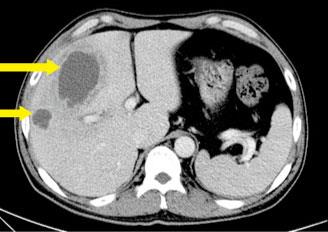

| △ 간에 고름이 찬 모습. 노란색 화살표 부위가 고름이다. |

간에 고름이 찼을 때의 초기 증상은 발열과 오한, 피로 등으로 몸살과 비슷하다. 병이 진행됨에 따라 손으로 배를 눌렀을 때 통증을 느끼게 되지만 이를 환자 스스로 알아차리기는 쉽지 않다. 따라서 간담도 질환이나 당뇨가 있는 사람 중에 발열과 오한, 복통 등이 수일 동안 지속된다면 화농성 간농양을 의심해볼 필요가 있다. 간농양은 혈액검사와 초음파, 컴퓨터 단층촬영(CT) 등을 통해 진단된다.